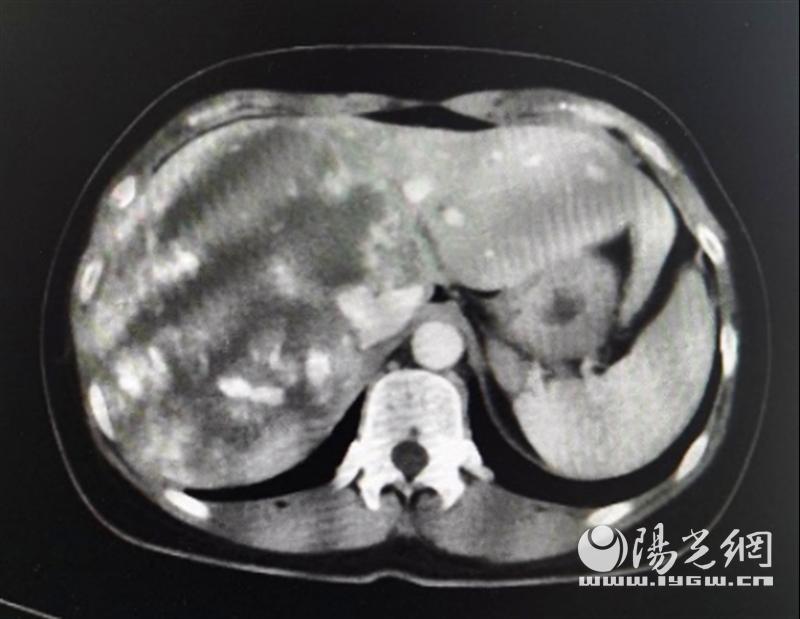

来自咸阳市的李女士,现年42岁,2个月前,她自觉上腹部疼痛,在当地医院检查后发现肝右叶有巨大占位性病变,疑为肝血管瘤。肝血管瘤是最常见的肝脏良性肿瘤,绝大多数患者并无症状,常常因为体检时查B超才发现。常见的肝血管瘤大多较小,直径超过10cm的就称之为巨大肝血管瘤,像李女士这样直径25cm大的则非常少见。

在慎重评估后,姚英民教授决定将李女士收住院,为其进行手术治疗。李女士入院后,肝胆外科姚英民教授、沙焕臣副教授对患者血管瘤病灶进行了精准术前评估。李女士所患血管瘤主要位于肝右叶、左内叶(IV段)及尾状叶,同时与第一肝门、第二肝门重要管道关系密切,推压变形,手术难度和风险非常之大。但手术治疗对患者非常有必要,这么大的血管瘤位于肝脏多条管道的纵横交错部,万一发生破裂,急诊处理会非常被动,很容易危及生命。